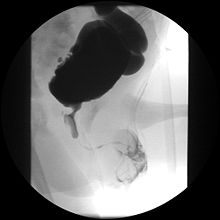

Cystourethrograph showing bladder obstruction with dilation of urethra and bladder

Ultrasound imaging can give information on the shape of the bladder, post-void residual volume, and evidence of kidney damage such as kidney size, thickness or ureteral dilation. A voiding cystourethrography study uses contrast dye to obtain images of the bladder both when it is full and after urination which can show changes in bladder shape consistent with neurogenic bladder.[9]